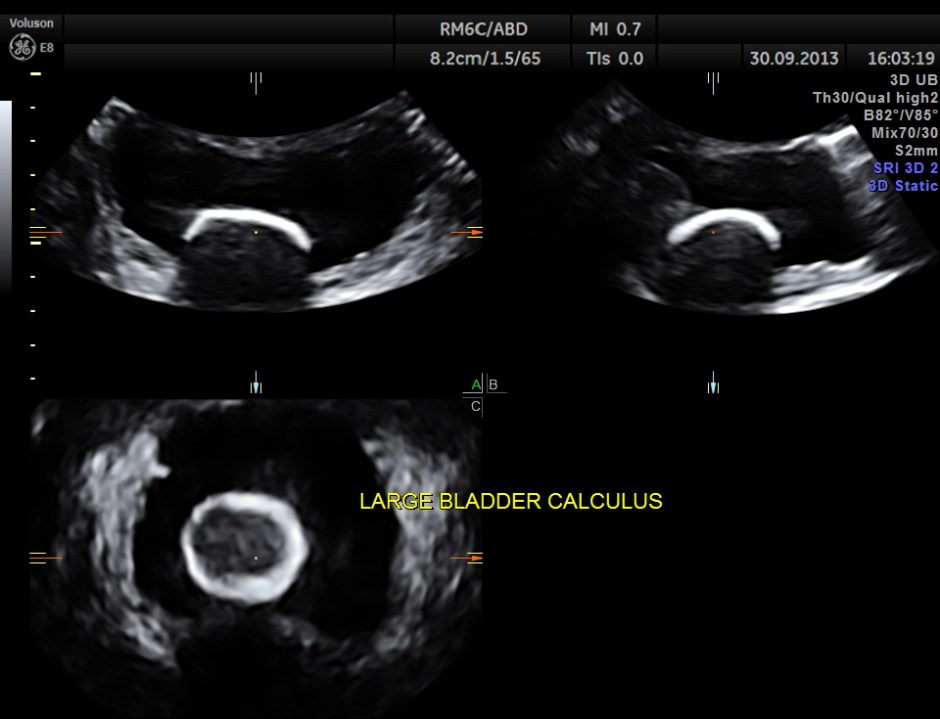

urinary bladder showed a large calculus and prominent swelling of the median lobe of the prostate.

multi- planar view of the bladder calculus

The diagnosis given was Large calculus in the urinary bladder , Severe prostatic enlargement with prominent median lobe hypertrophy , causing Right sided obstructive uropathy.

The diagnosis was made with the 2D images , but the 3 D images were very helpful in explaining to the patient.